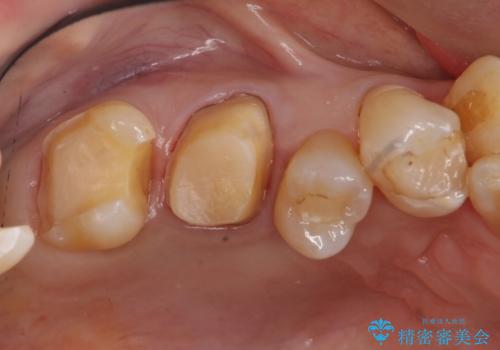

- 奥歯の詰め物のやり替えを希望して来院。

銀歯と、プラスチックをセラミックにかえました。

古い詰め物を取るときに、しっかり虫歯はとっています。

右上6番は詰め物が大きく、インレーではなくクラウンとしました。